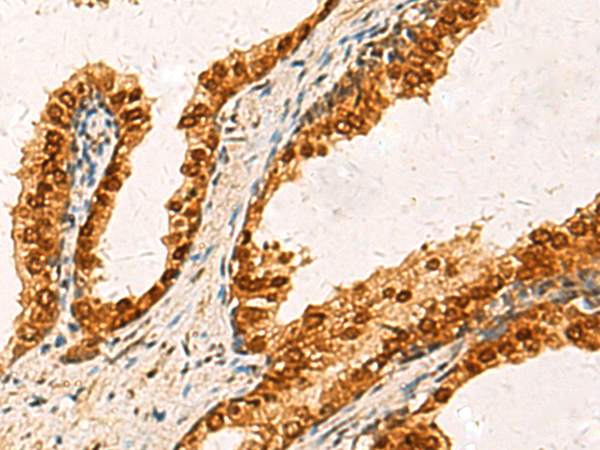

分类: 科研抗体货号: P03397别名: FADS; CMS11; CMS4C; RAPSYN; RNF205应用: WB,IHC反应种属: Human, Mouse